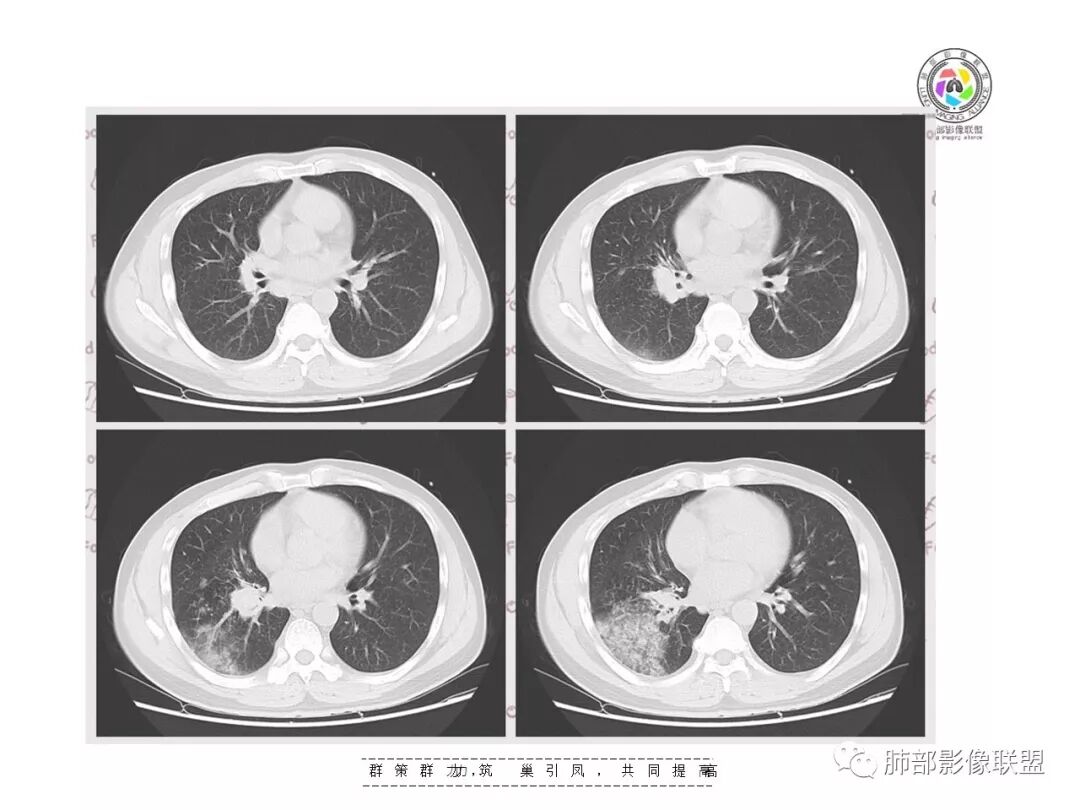

【影像资料】

右肺门区淋巴结增大,融合,密度均匀,均匀强化

复查胸部CT视频显示肺部病灶明显吸收,淋巴结较前缩小。

患者在本院做了支气管镜,报告是有新生物,取了活检就转院了。病理结果是后来出来的。去肿瘤医院再做支气管镜,病理还是炎症。抗炎治疗(电话追问患者家属,具体不详)一个月后复查,右下肺病变基本吸收,肺门肿块明显变小;纵隔淋巴结基本都没了或者明显变小了

淋巴结肿大常见那么几种病变,转移瘤不符合,影像右下肺病变为炎性病变征象,前面已描述其特征:形态、走形、边缘(实质和GGO)、中央间质增厚、均匀强化、支气管充气征。都符合急性炎性病变。

支气管走形分布其实就两个问题。支气管远端部分堵塞,但大部分见支气管充气征明显。首先病变累及到支气管,支气管充气征远端病变常见两大类病变,气腔性的和引起气腔改变的,肺实质和支气管来源的均可以。

有树芽征,树芽征一般提示小气道受到影像,是炎性病变的特点。周围很多磨玻璃影,一般提示炎性病变,考虑急性为主,最起码有急性病变在其中。但该病人存在一个问题,其前基底段支气管有扩张,周围有实变,考虑原有病灶,有支气管扩张一般不考虑恶性肿瘤,肯定是慢性炎性病变。